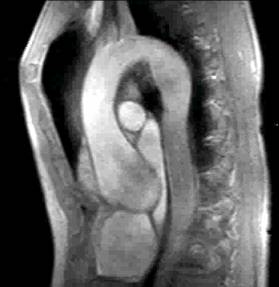

1) This gradient echo cine shows which of the following abnormalities?